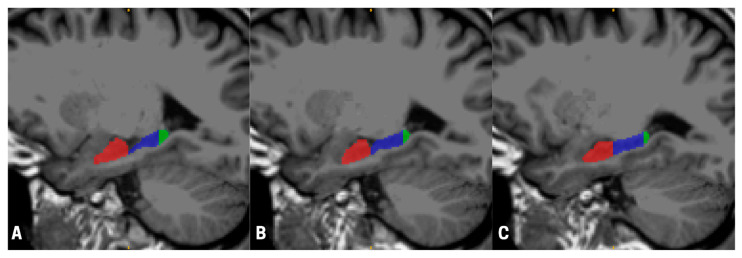

(1) Background: Evidence from non-human animal and spaceflight analog studies have suggested that traveling to outer space could have a significant impact on the structural properties of the hippocampus, a brain region within the medial temporal lobe that is critical for learning and memory. Here, we tested this hypothesis in a group of astronauts who participated in a six-month mission in the International Space Station (ISS). (2) Methods: We collected magnetic resonance imaging (MRI) scans from a sample of 17 (9 males, 8 females) astronauts before and after the ISS mission, and calculated percent gray matter volume changes in the whole hippocampus and its (anterior, body, and posterior) subregions in both hemispheres. (3) Following the six-month mission in the ISS, we found a significantly decreased volume in the whole left hippocampus; in addition, when looking at subregions separately, we detected a significantly decreased volume in the anterior subregion of the left hippocampus and the body subregion of the right hippocampus. We also found a significantly decreased volume in the whole right hippocampus of male astronauts as compared to female astronauts. (4) Conclusions: This study, providing the very first evidence of hippocampal volumetric changes in astronauts following a six-month mission to the ISS, could have significant implications for cognitive performance during future long-duration spaceflights.

Abstract Image